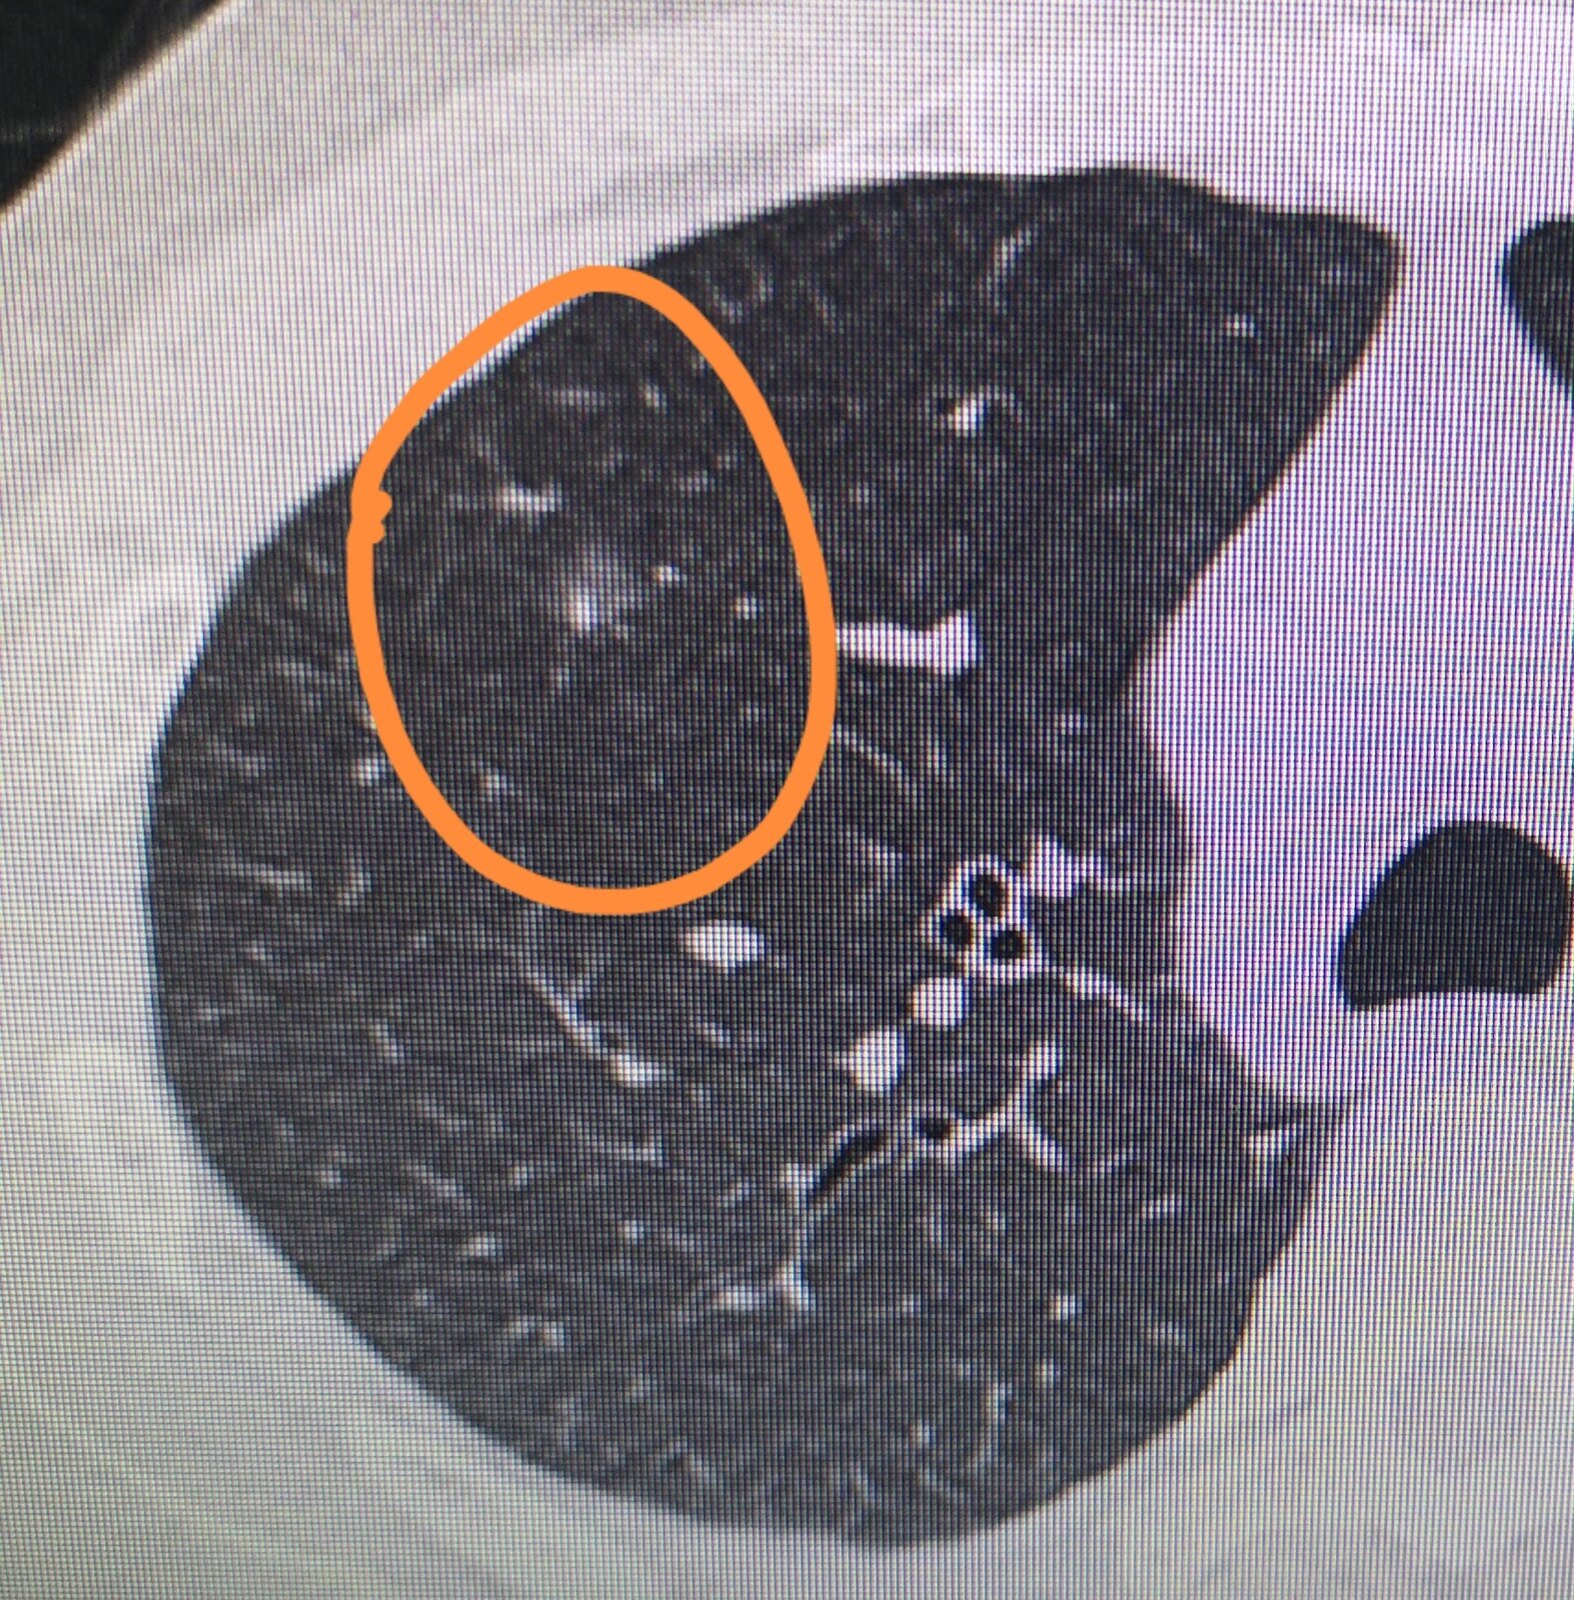

肺曲霉菌病

X射线检查的特点是有圆形或椭圆形的均匀不透明区域。典型的CT图像是新月形空气周围有致密的结节阴影。结节阴影常可随体位在腔内的变化而移动。